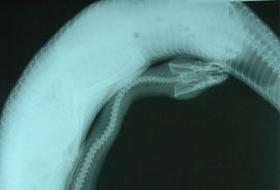

Görenleri şaşkına çeviren fotoğraf!